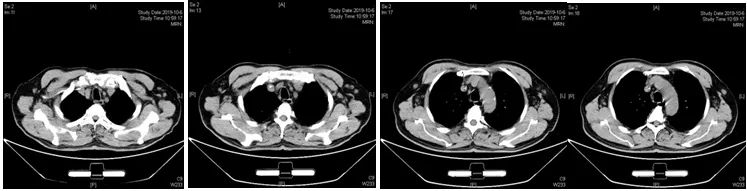

2019-10-06

行颈胸腹盆腔部位加强CT,中期疗效为PR